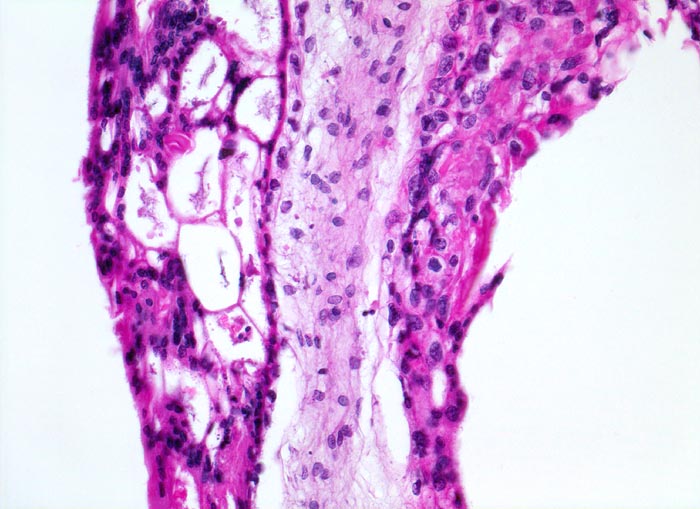

Makroskopisch ist die Plazenta deutlich grösser als erwartet für das Schwangerschaftsalter. Sie ist diffus von bis 2cm grossen Zottenblasen durchsetzt, welche nach Kollaps jedoch der makroskopischen Entdeckung entgehen können. Beim Aufschwemmen in Flüssigkeit entfalten sich die Blasen wieder. Mikroskopisch sind die Zotten aufgrund einer grobblasigen pseudozystischen Hohlraumbildung im Zottenstroma überwiegend grosskalibrig. Im Zottenstroma sind nur ganz vereinzelt Kapillaren nachweisbar. Im Gegensatz zu hydropisch geschwollenen Zotten im Sinne eines Regressionsphänomens zeigen die Zotten bei Blasenmole zusätzlich eine zirkumferentielle Hyperplasie von Synzytio- und Zytotrophoblast mit fakultativer Zellatypie. Bei herdförmiger Mole (> 3725) sind diese Veränderungen nur in einem Teil der Plazentarzotten ausgeprägt.

• Hydropisch umgewandeltes Zottenstroma ohne Gefässe mit Ausbildung von pseudozystischen Hohlräumen (Blasen)

• Trophoblastinklusionen und Kerntrümmer im Zottenstroma.

• Überschiessend proliferiertes Trophoblastepithel, teils in der gesamten Zirkumferenz der Zotten mit deutlichen Kernatypien. Kein Embryo.